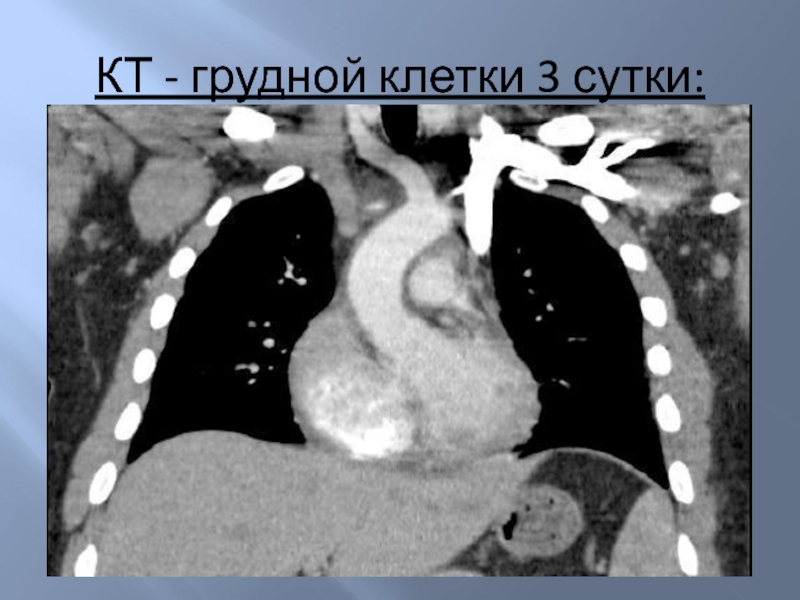

Слайд 14КТ - грудной клетки 3 сутки:

КТ - грудной клетки 3 сутки: